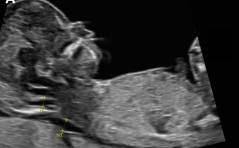

Sonoquiz

Was ist das? PDF Dokument